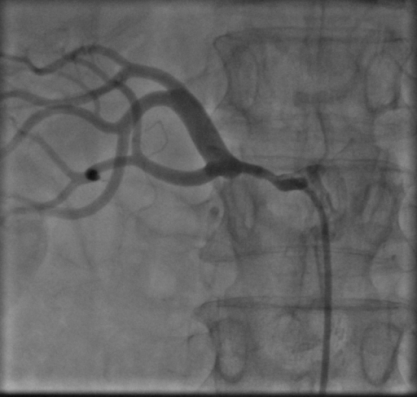

患者女性,57岁,突发上腹疼痛伴呕血,在pilipili 住院后经止血、补液等对症治疗,呕血仍没得到完全控制,血色素持续降低,行急诊胃镜提示消化道溃疡并出血,经多学科会诊后,认为应以介入手段进行腹腔动脉造影+备出血动脉栓塞术。经刘稳棠医生细心沟通及讲解手术方案,积极与患者及家属沟通并取得同意后,立即通知介入室行急诊介入止血治疗。

术中造影发现胃十二指肠一分支动脉渗血,随后应用栓塞剂进行栓塞,造影复查出血动脉未见显示,止血成功。术后患者症状改善,未再出现呕血、血色素上升,生命体征平稳。